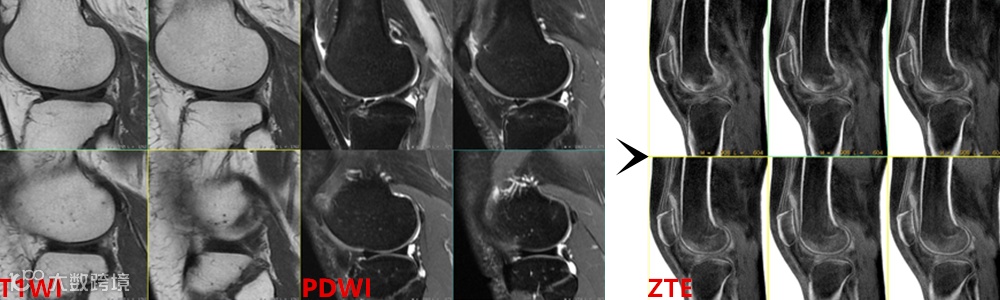

ZTE序列通过其独特的成像原理,改变了骨皮质在传统MRI序列上总是“沉默的黑色”的现状,能像CT一样清晰显示其骨质细节,实现了对传统MRI序列“盲区”——超短T2(横向弛豫时间)组织的直接成像,被广泛用于骨骼、血管,肺实质等结构的成像。

ZTE改变了骨皮质在传统MRI序列上总是“沉默的黑色”的现状,能像CT一样清晰显示其骨皮质细节。

对比度特性:由于TE极短,图像基本消除了T2权重,初始对比度以质子密度加权和T1加权为主。通过对原始图像进行后处理(将获得原始图像灰度反转后的“负图”),可以使骨皮质等致密组织呈现类似CT的高信号,实现“类CT”成像效果。

经过从黑到白的灰度反转后,能产生与X线片或CT极为相似的对比度,从而实现直观的“类CT”视觉效果。